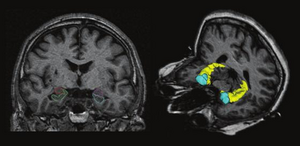

The regions-of-interest (ROIs) were manually drawn by an experienced radiologist by using the b 1000 images, averaged for all measured directions, the FA maps and the proton-density weighted images. For that purpose, the maps of ADC, FA, R2 and R2* as well as the proton-density weighted images were first co-registered. The ROIs were segmented by syncing the b 1000 images, averaged for all measured directions, the FA maps and the proton-density weighted images in ImageJ. The ROIs were stored in the ROI manager and transferred to the co-registered maps. The segmented brain regions were highlighted in different colors: CN—black; PU—red; GP—green; TH—white; SN—blue; CC—cyan. The diffusion-weighted images, the R2 and R2*-weighted maps were transferred to the 3D Slicer software in order to co-register the R2 and the R2* maps as well as the MD and the FA maps |

MRI with labeled structures from atlas registered to the CBCT. Registration was carried out with the open source imaging tool 3D Slicer, Version 4.4.0. |